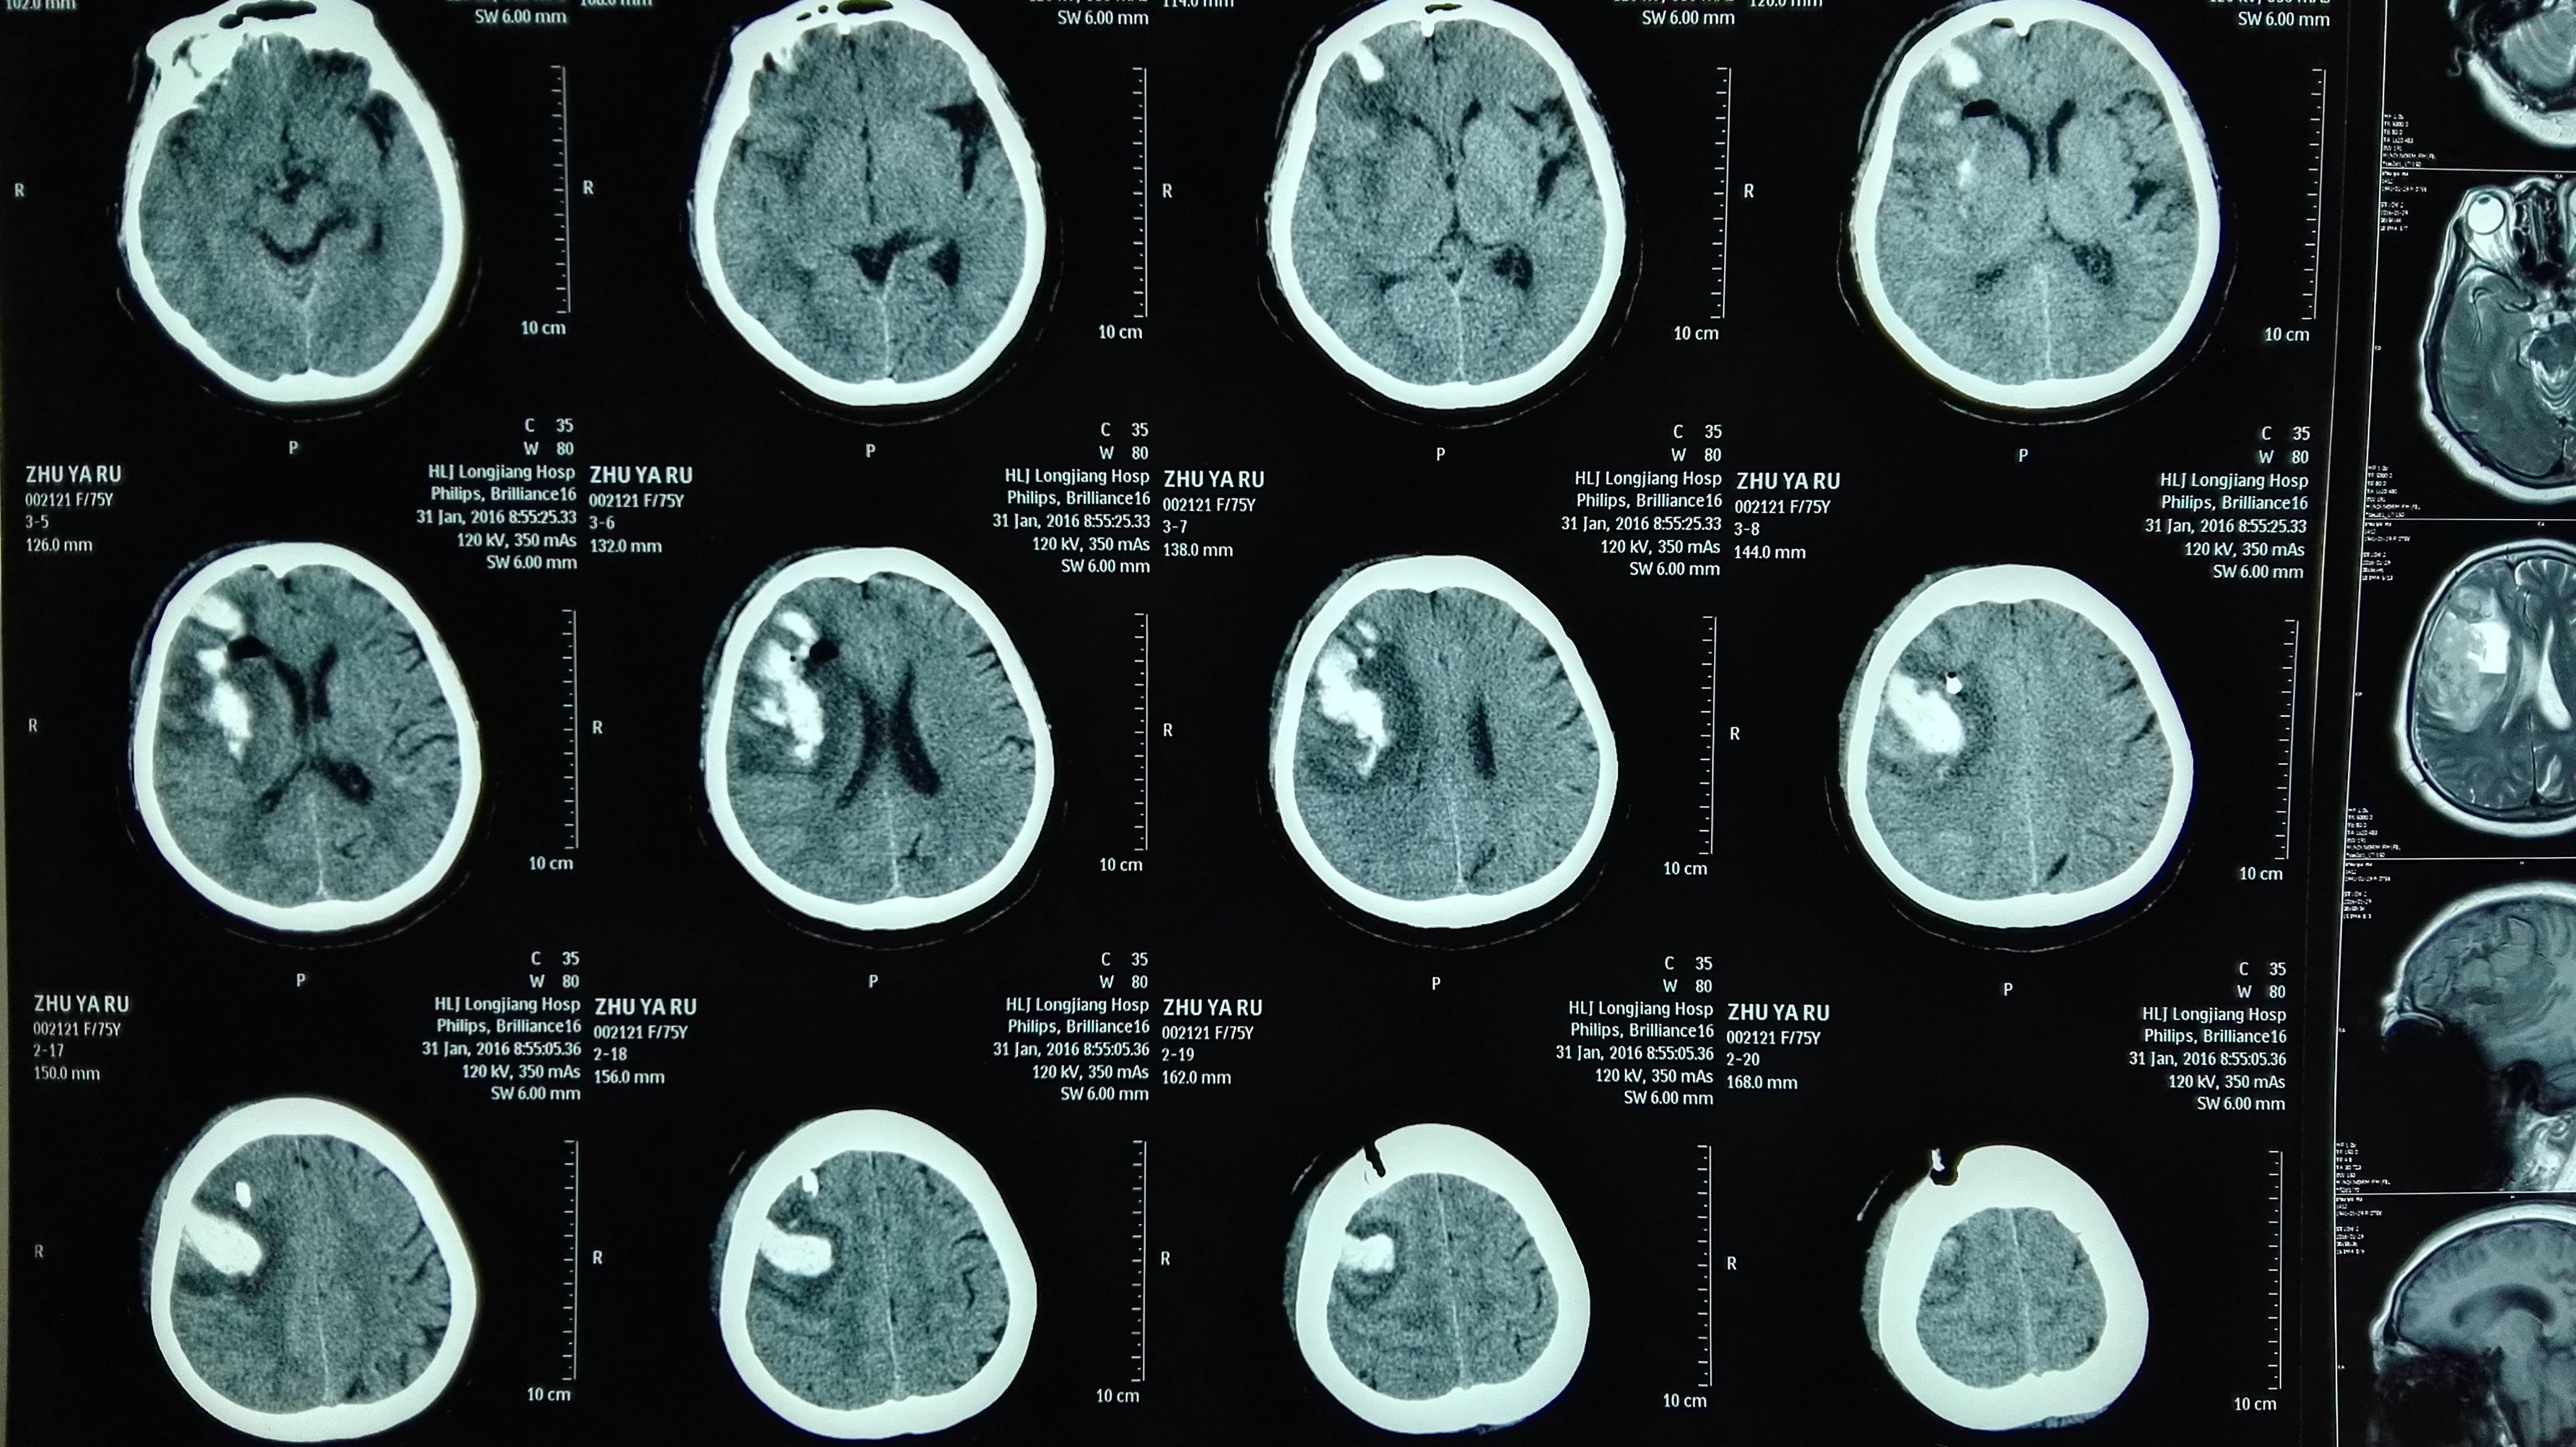

脑出血ct图

以突发脑出血入院,入院头颅ct提示右侧顶枕部出血52ml.

头颅ct提示:左侧基底节区脑出血.出血量大于30ml.

ct提示左侧基底节,丘脑,颞叶,枕叶广泛性脑出血.

患者入院头颅ct显示为左侧颞枕叶脑出血,出血量大